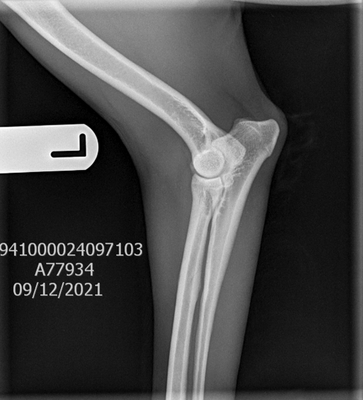

Elbows: Elbows are graded individually with a score from 0-3 on each side. The ideal being a score of 0. To have an elbow scored there must be at least two x-rays; flexed lateral and neutral view. Elbow dysplasia is uncommon in both Komondor and Mudi.

Patella Luxation

A patella luxation exam can be done during a routine vet visit! No sedation is required. The vet should check both patellas and give them a grade from 0-4 based on the Putnam 1968 scoring system. Excessive force should never be used when manipulating the patella. For us, we have our vet recheck Patella during each yearly check at the same time that we are doing annual eye exams.

Grade 0: Normal

Grade 1: The patella can be manually luxated with the stifle in full extension, but when pressure is released without manipulation of the limb the patella regains its original position in the trochlea. Spontaneous luxation of the patella during normal joint motion rarely occurs. Typically stifle and hock in a straight line with no deviation of the hock.

Grade 2: the patella can be completely luxated, but manipulation of the hind limb (flexion of the stifle) causes the patella to regain its original position in the trochlear. On physical examination, the patella luxates easily, especially when the foot is rotated.

Grade 3: the patella is found (at least once) spontaneously luxated with the animal in a standing position or it is permanently luxated but can be repositioned manually or by manipulating the limb. Very shallow or flattened trochlear.

Grade 4: the patella is permanently luxated and cannot be repositioned. May scarcely be able to walk or may move in a crouched position with both limbs partially flexed, and/or they may carry the affected limb. Trochlea is shallow, absent or even convex.